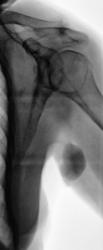

Итак произведена рентгенография плечевого сустава в прямой проекции.

Снимок выдан "наруки" внучке, которая "понеслась" к хирургу. Через 10 минут - звонок от хирурга с вопросов - "А что это за чертовина?"

Валентин Львович! Классный случай! Особенно с точки зрения общения врачей-лечебников и рентгенологов! А подмышкой у бабушки мне видится лимфоузел. Кости то, слава Богу, целы. А что "добрый доктор" пальпировал у пациентки при осмотре?

Но лимфоузел в подкрыльзовой ямке пролетает, как "фанера над Парижем".

взгляд - это гематома.

"Фанера" над городом Парижем летит дальше. Нет, не гематома.

неужели страшная волосатая бородавка?!

Да не ошиблись, попали в точку. А что нет волос, так "волосы" - придатки кожи. Да и не нужны бабулечке уже никакие "придатки".